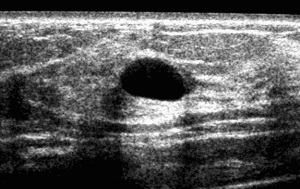

- As imagens se apresentam com forma bem definida, contorno regular ou bocelado, limites precisos, orientação horizontal, discreto ou acentuado reforço acústico posterior, sombra acústica bilateral ou ausente e ecotextura homogênea, podendo ser anecóicas, hipoecóicas ou isoecóicas. Cistos, nódulos com componente de gordura (inclusive linfonodos intramamários), nódulos com calcificação “em pipoca”, típicos de fibroadenomas;

- Cistos completamente anecóicos ou com septos finos ou com grãos de cálcio em suspensão ou com debris móveis ou com nível de gordura/líquido (cistos lipídicos).

- Nódulos sólidos, não-calcificados, ovóides, com orientação paralela à pele, sem achados acústicos posteriores (podem, eventualmente, apresentar discreto reforço posterior) e que ainda não completaram 2 anos de estabilidade.